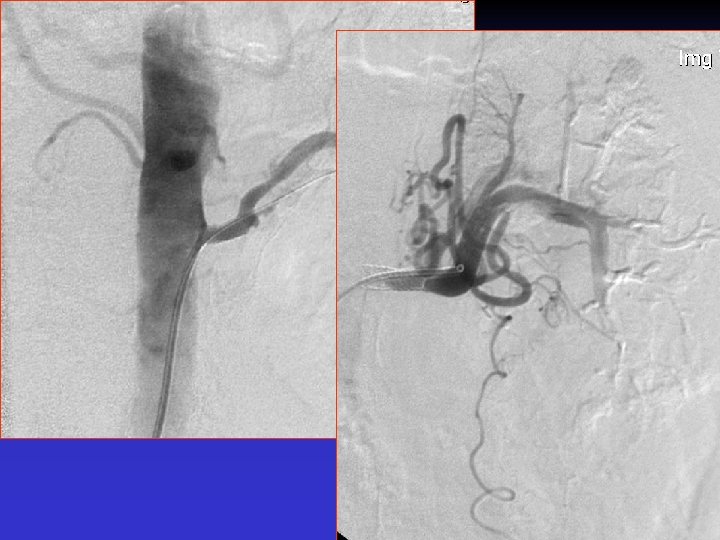

Case #1 S/p EVAR new onset of HTN

Case # 2 • 50 -year-old male with solitary kidney. • Smoker. • Refractory HTN. • Cr: 3. 8 mg/dl

• B/P: 160/80 mm. Hg • Cr: 1. 8 mg/dl

The patient was re-admitted 18 months later with Cr: 2. 8 mg/dl, and BP: 180/90 mm. Hg.